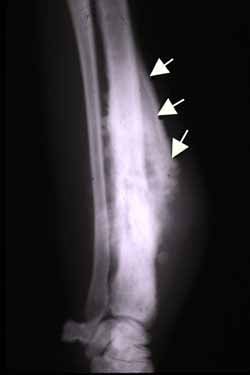

Type III: Permeative (cortical destruction, no defined margin) = highly aggressive malignancy

- "Ewing sarcoma: diaphyseal in children, permeative, lamellated (onion-skin) periosteal reaction, large soft tissue mass. Peak age 5-15.

The single most important radiographic feature is the MARGIN of the lesion, classified by Lodwick: Type IA — geographic destruction with a well-defined sclerotic rim. This is the classic appearance of benign lesions (non-ossifying fibroma, enchondroma, simple bone cyst). The sclerotic rim indicates the host bone is keeping pace with the lesion's growth. Type IB — geographic destruction with a well-defined margin but NO sclerotic rim. This suggests a low-grade malignancy or aggressive benign lesion (GCT, chondrosarcoma). Type IC — geographic with an ill-defined margin. Intermediate aggressiveness. Type II — moth-eaten pattern (multiple small lytic areas without defined margins). Moderately aggressive malignancy. Type III — permeative pattern (cortical destruction without any defined lesion margin). Highly aggressive — Ewing sarcoma, osteosarcoma, lymphoma, metastases.

| Ewing sarcoma | Diaphyseal (in children), permeative, lamellated (onion-skin) periosteal reaction, LARGE soft tissue mass | Permeative destruction + large soft tissue mass disproportionate to bone lesion. Peak age 5-15 |

- •Ewing: diaphyseal, permeative, onion-skin, LARGE soft tissue mass, age 5-15